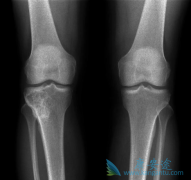

既往骨折史是未来脆性骨折强有力的预测因素之一。在FREEDOM研究中, 地诺单抗 (denosumab)可以显著降低患者新发椎体、非椎体以及髋骨骨折的风险。FREEDOM事后分析,旨在阐明地诺单抗在既往有骨折史的受试者二次脆性骨折预防中的疗效。共计8087名女性被 ...